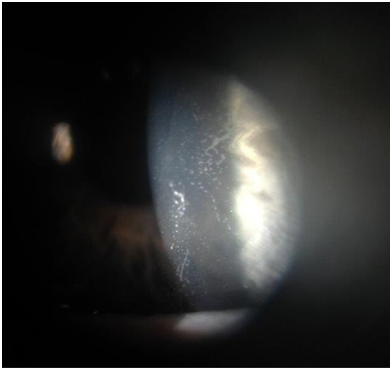

Figure 1Slit lamp photograph of left cornea demonstrating epithelial ingrowth under the midperiphery of the LASIK flap with direct extension into the visual axis.

In the current case, epithelial ingrowth resolved on slit lamp exam after flap lift, debridement, and drop treatment; visual symptoms did not return. How the epithelial cells were introduced under the corneal flap remains unclear. Traumatic crystalline foreign bodies at the LASIK flap interface without flap displacement has been reported. Choi postulated that a sharp, high velocity, but weak ocular trauma could open the potential stromal space and leave debris without displacing the flap.20 We speculate a similar mechanism occurred with this patient or that the twig may have microscopically penetrated to the interface, implanting surface epithelial cells into the potential space. Cellular proliferation may have given the patient their presenting symptoms. Although corneal slit lamp examination is the standard for detecting epithelial ingrowth, anterior segment optical coherence tomography (OCT) may be a useful diagnostic tool. OCT may evaluate corneal structure changes related to disease before surgical debridement.21 After treatment, careful monitoring with close follow-up in these patients is necessary. Higher rates of recurrence even after surgical debridement have been reported.22 Post-traumatic epithelial ingrowth introduces cells into the corneal flap interface and corneal disturbance is observed. In this report, however, epithelial ingrowth occurred beneath the flap without any sign of disruption. This report exemplifies the need for close follow-up and examination of all LASIK patients even after minor trauma, since corneal anatomy is indefinitely altered. Ophthalmologists should educate patients on epithelial ingrowth as a post-operative complication and carefully monitor patients for signs, regardless of observed flap disruption or distant chronology from the initial LASIK procedure.